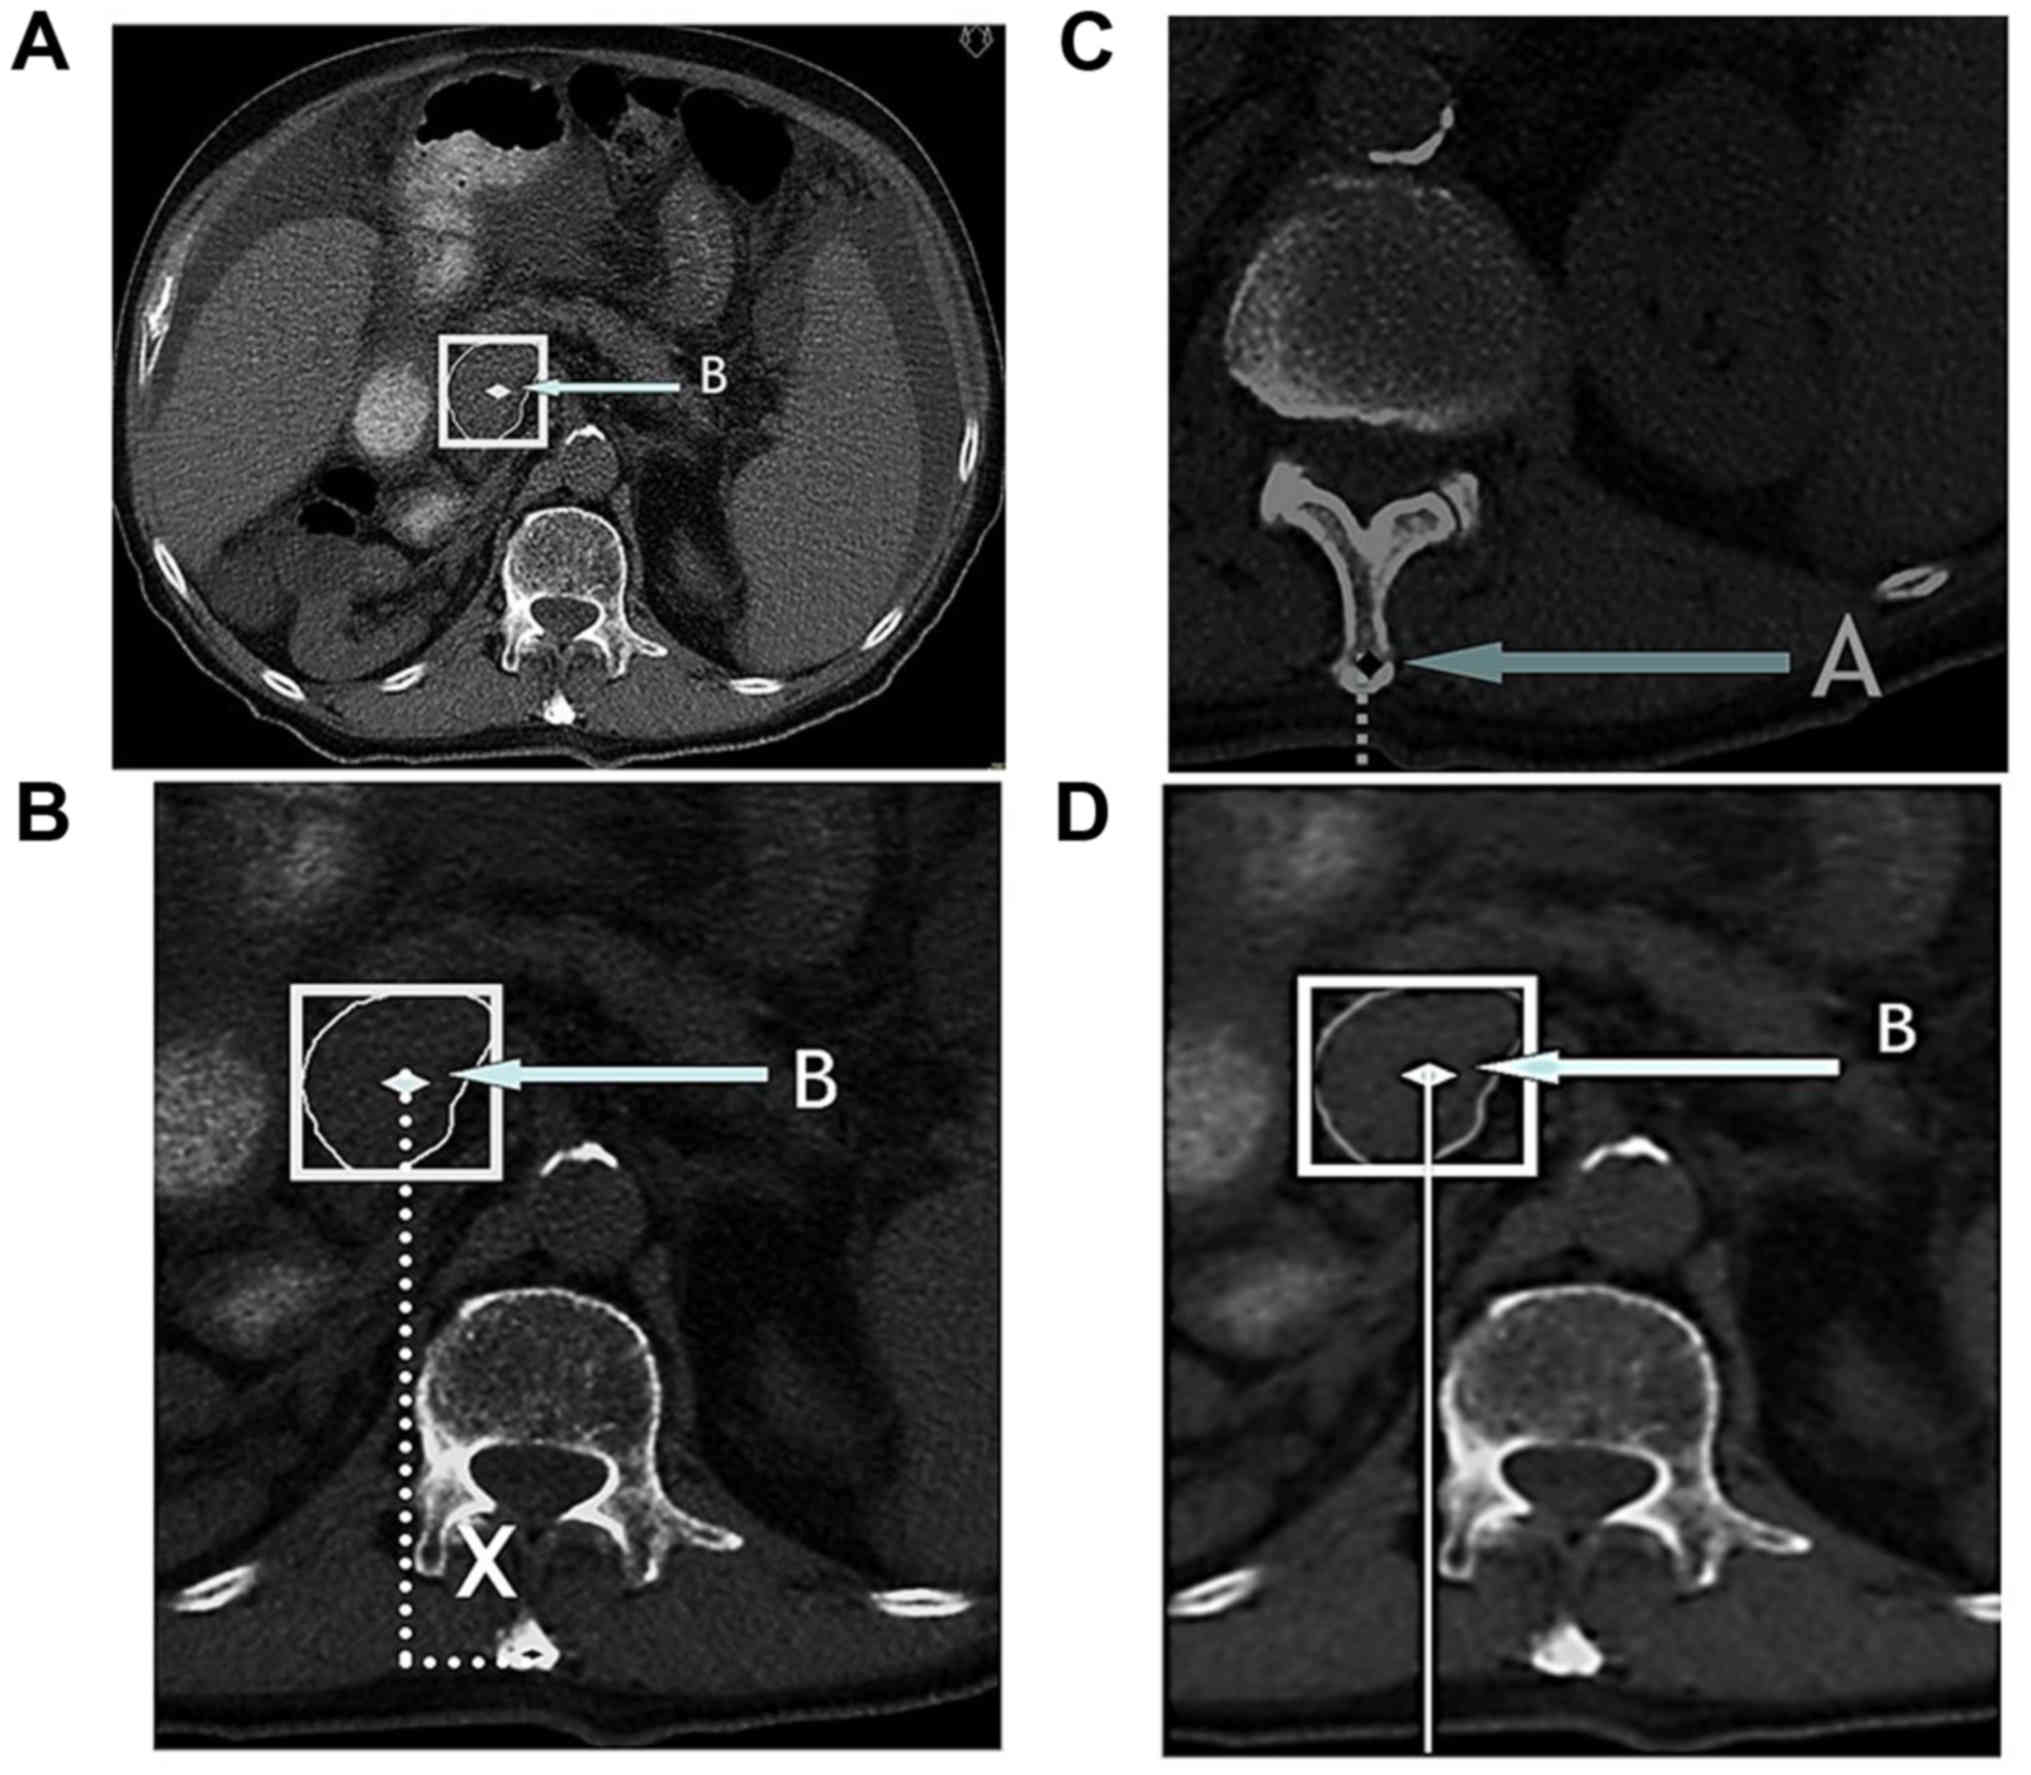

CT scans with the patient in the same position for treatment reproducibility were performed (Table I), extending from T9 to L5 with an interval between scans of 5 mm. CT images were printed with a scale indicator display. The tumor had to be identified on all scans where it was visible. The scan displaying the center (in cranio-caudal direction) of the tumor was identified. The geometric center of the tumor [defined as the center of the rectangle circumscribing the visible tumor mass] (Fig. 2A) was indicated on this scan. This point was defined as point B.

CT reference points and measurements for 2D conformal planning. (A) CT image at the tumor center (in cranio-caudal direction). The point B is defined as the geometric center of the rectangle circumscribing the tumor; (B) measurement of the lateral distance between point B and the center of the lumbar spine [used as the lateral distance between point A and point B]; (C) measurement of the distance of point A from the couch; (D) measurement of the distance of point B from the couch. The difference between the two distances was used to define the distance in anterior-posterior direction between point A and point B.

Then, the distance in 3 dimensions (x, y, z) between point A and point B was calculated: i) The distance of point B from the center of the lumbar spine was measured, which corresponds to the lateral distance from point B to point A, if the patient is correctly aligned (distance x, Fig. 2B); ii) the cranio-caudal distance was calculated as the distance between the level of the scan in which point A and B were visible (distance y); iii) the antero-posterior distance was defined by measuring the distance between point A and B from the CT bed and then calculating their relative difference (distance z, Fig. 2C and D);.

Another simulation was then performed. Using the distances between point A and point B, the simulator table/bed with the patient was moved to align point B (center of the target) with the simulator isocenter. Two new X-rays centered at point B, one in the anterior-posterior projection and the other in lateral projection, were taken (Fig. 3A and B).